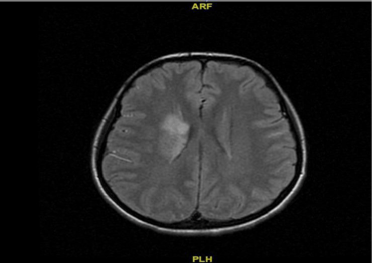

Double Valve Infective Endocarditis Presenting with Acute Ischemic Stroke

Infective endocarditis is a potentially fatal infectious disease which usually presents with various clinic scenarios. Although the disease generally presents itself with fever, cardiac murmur (bruit), splenomegaly and anemia; in this case we report a double valve endocarditis of a 23 years-old female patient who was admitted to our neurology clinic with acute ischemic stroke.